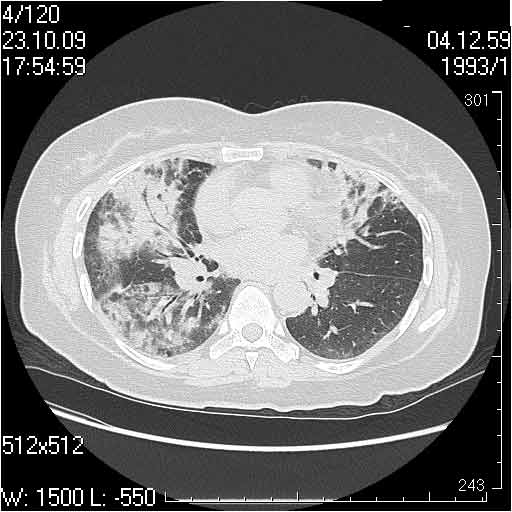

Случай №3

Женщина 51 год

Случай 3:смешанные изменения; подходят для интерстициальной пневмонии, тактика аналогична случаю 1.